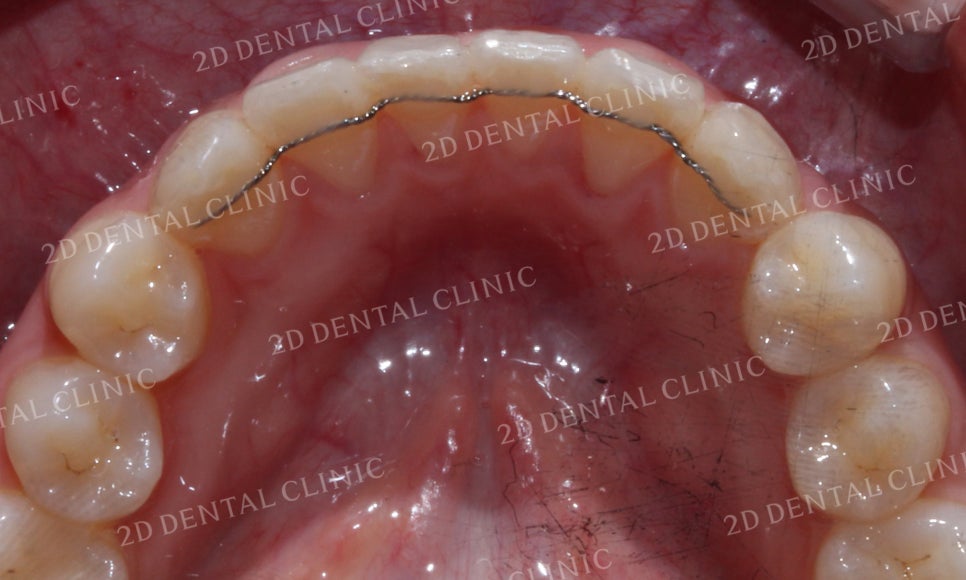

앞니교정 전 치아의 모습을 보시면

미소 시 중절치가 토끼처럼 튀어나온

모습을 확인할 수 있었는데요,

토끼앞니 교정 후 중절치의

돌출감이 사라지면서

치열이 고르게 바뀐 모습입니다.